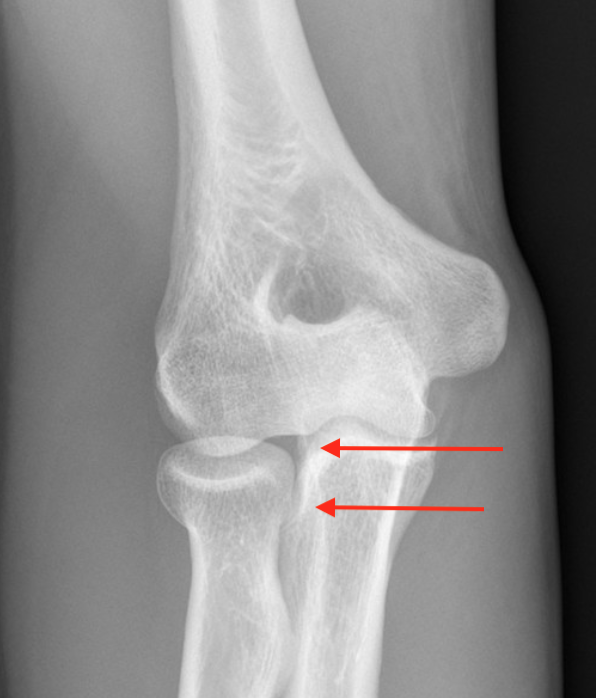

Overstuffing

| Lesser sigmoid notch | Symmetry of ulnohumeral joint |

|---|---|

|

Radial head shoulder articulate with lesser notch

Ensure no gapping of lateral ulnohumeral joint |

- cadaveric study

- increased medial ulno-humeral joint line gapping with overlengthening of 6 or 8 mm

- increased lateral ulno-humeral joint line gapping with overlengthening of 2 mm